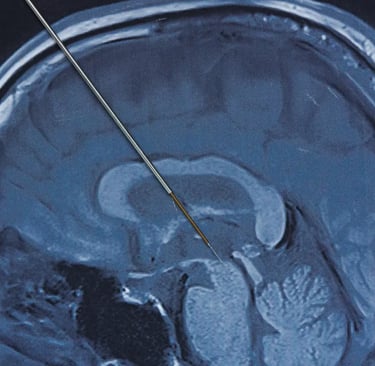

Un ejemplo que mencionan en el artículo del MIT Techonlogy Review es el de la enfermedad de Parkinson. En la que existen estructuras específicas dentro del cerebro que son las encargadas de las funciones motoras de nuestros cuerpos. Bajo condiciones muy específicas se puede utilizar la Estimulación Cerebral Profunda, para brindar pequeñas y controladas descargas eléctricas, en zonas muy específicas, con lo que se ayuda al paciente a mejorar sus capacidades motrices y por supuesto, mejorar su calidad de vida.

A inicios del milenio (en los años 2000’es) se llevaron a cabo grandes ensayos clínicos en los que buscaban utilizar ésta tecnología (la Estimulación Cerebral Profunda, o DBS por sus siglas en inglés) como tratamiento para la depresión severa resistente a los tratamientos tradicionales. Sin embargo los ensayos fueron suspendidos de forma anticipada por la ausencia de resultados positivos.

Sin embargo en el 2020 -inicios- un grupo de investigadores decidieron cambiar la perspectiva de los ensayos predecesores. Implantando 2 electrodos de DBS a cada lado de su cerebro, en las zonas convencionalmente asociadas a los síntomas de la depresión, a un primer voluntario. Adicionalmente 5 electrodos temporales fueron puestos en cada lado de su cerebro para monitorear su actividad en las regiones vinculadas con el estado de ánimo y los procesos cognitivos.